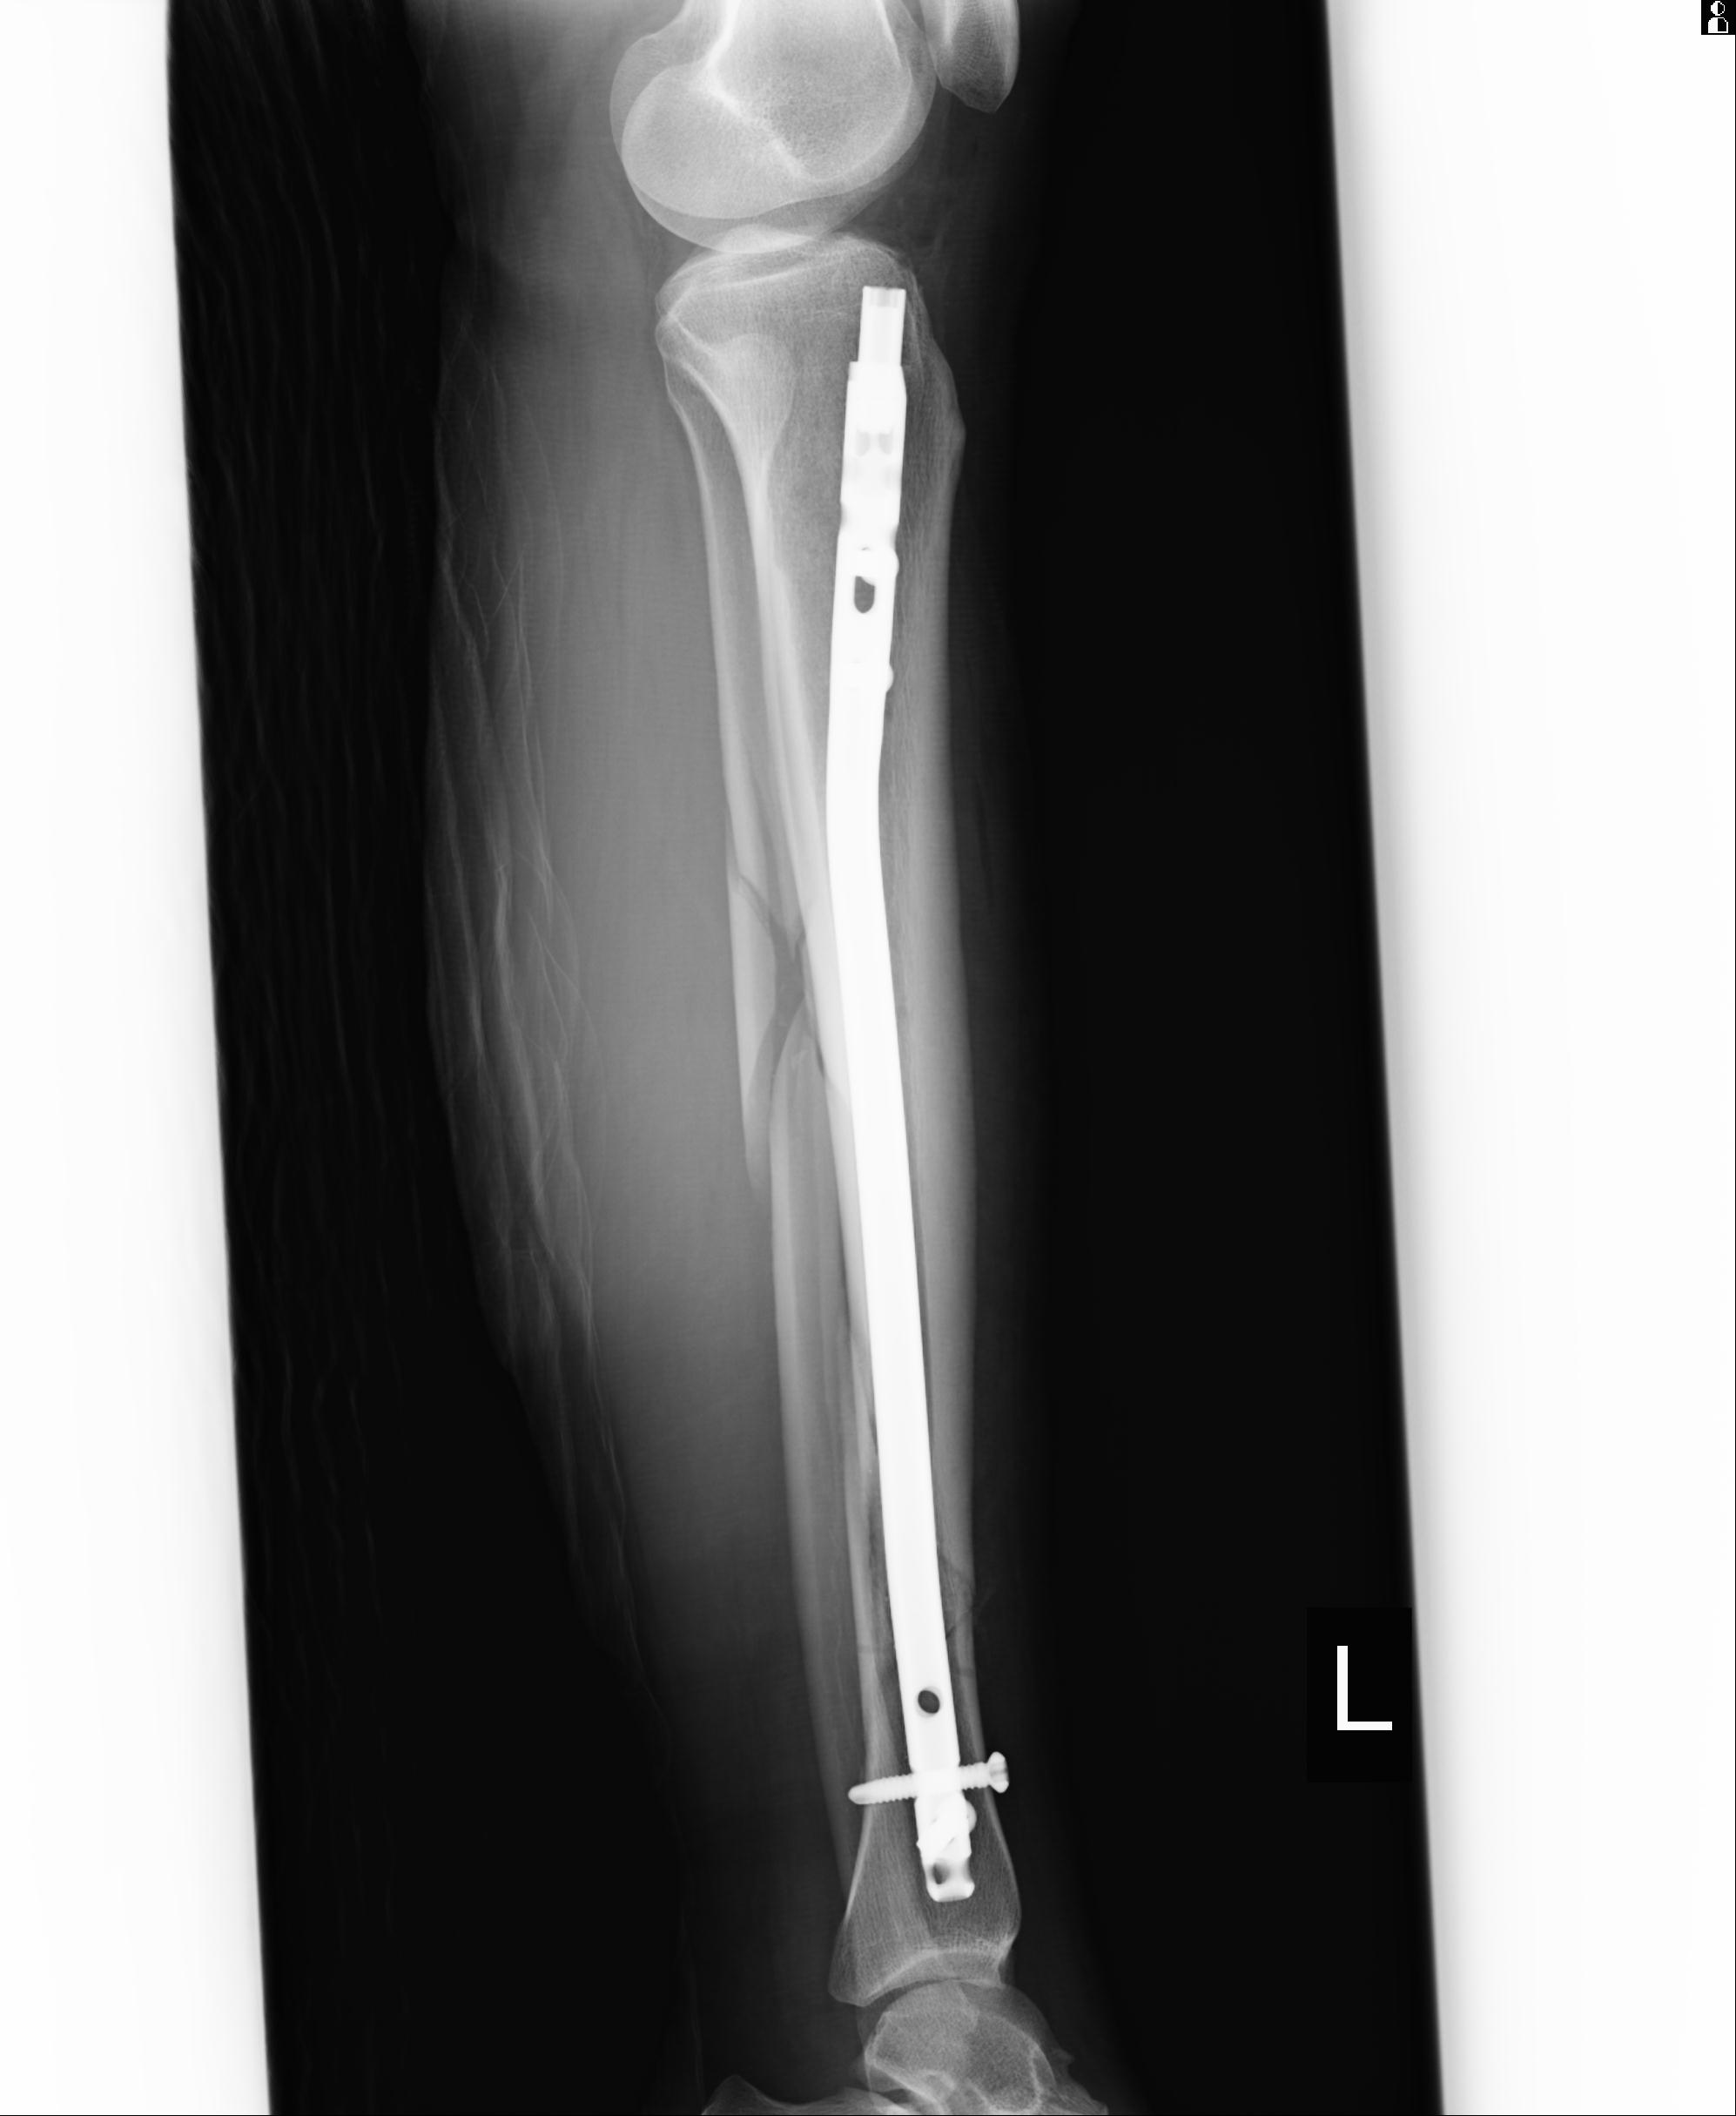

102803 1/12(キウスなし) 1/27 左下腿 4R 30歳女性 左脛骨軸内釘